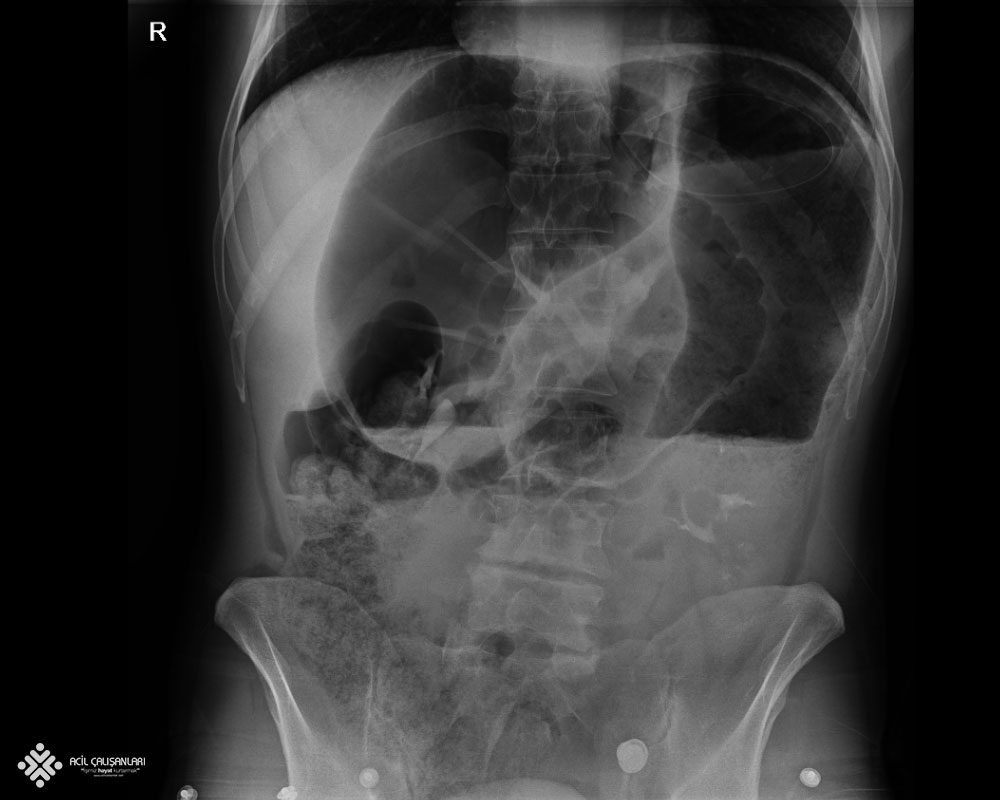

70 yaşında erkek hasta şiddetli karın ağrısı nedeni ile acile başvuruyor. Hastanın öyküsünde karın ağrısının bugün başladığını, gaz çıkardığını ama dışkılama bugün yapamadığını belirtiyor. Hasta sarı alan doktoru tarafından; GKS'u 15 Nabız: 80 atım/dk düzenli ; Ateşi 36,7 °C ; Solunum sayısı: 14/dk ; SpO2: 98 ; KŞ: 100 ve Kan Basıncı: 140/90 mm/Hg olarak değerlendiriliyor. Fizik muayenede; üst kadranlarda daha fazla olmak üzere yaygın karın hassasiyeti mevcut. Defans rebound yok. Rektal tuşede rektum boş, diğer sistemler doğal olarak değerlendiriliyor. Acil hekimi aşağıda görüldüğü gibi hastadan ayakta batın grafisi istiyor. Bu bilgilere göre bundan sonra hastaya uygulanacak en uygun yaklaşım ne olmalıdır?

D) Çekilen ayakta direkt batın grafisi volvulus olarak değerlendirilmeli ve oral alım durdurulmalı , nazogastrik sonda takılmalı ve genel cerrahi görüşü istenmelidir.

Sigmoid volvulusta grafide sigmoid kolon ve tıkanıklığın üst kısmında kalan kolon segmenti oldukça genişlemiş olarak saptanır. Bunun dışında yine konvansiyonel karın grafisinde kuş gagası, kahve çekirdeği belirtisi, ters U şekli veya omega ans belirtileri saptanabilir ve tanı koydurucu bulgulardır.